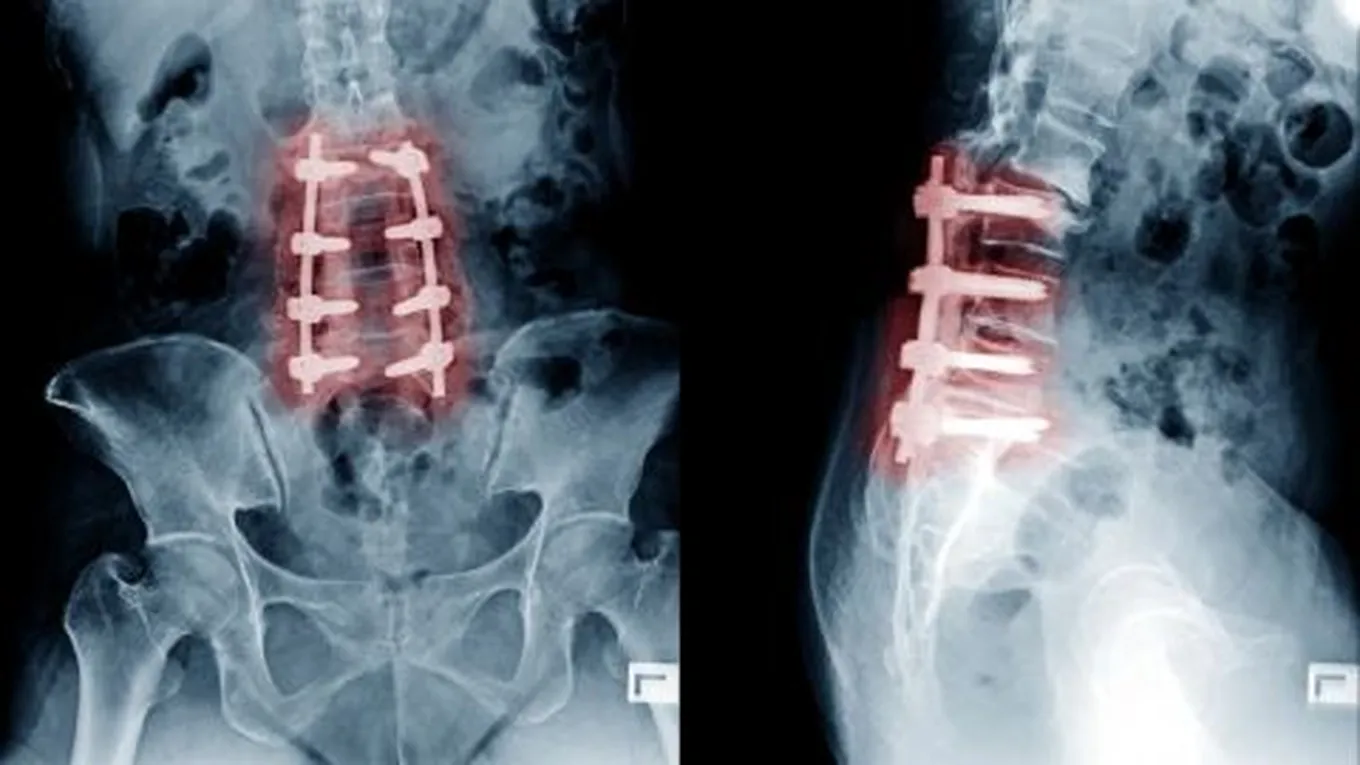

- إجراء العمليات الجراحيّة في الحالات المتقدّمة.